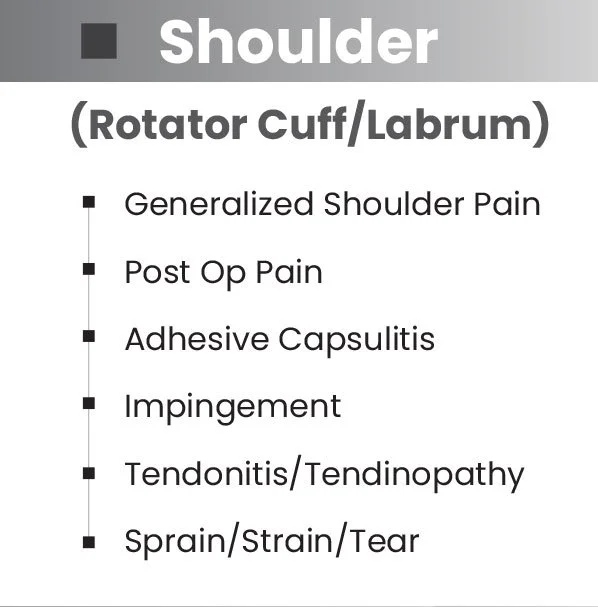

Effective Pain Reduction Across a Broad Range of Conditions.

Back, neck, shoulder, elbow and knee pain